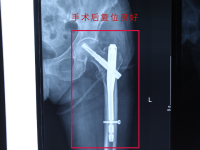

手术当日,骨伤科团队采用微创闭合复位PFNA(股骨近端防旋髓内钉)内固定术。在C型臂X光机实时引导下,仅通过两个不足3厘米的小切口,便完成了骨折碎片的精准复位与内固定植入,整个手术耗时不足1小时,术中出血量控制在50毫升以内,最大限度减少了对老人身体的创伤。“老年患者手术,‘微创’不仅是技术要求,更是对身体机能的保护,每一步操作都要精准到毫米。” 手术主刀医师、骨伤科王勇主任介绍。

“术后第二天就能在床上活动左腿,疼得也轻多了,腿也恢复到原来的长度。” 骨伤科王主任介绍,康复科已制定个性化康复计划,从踝泵运动、股四头肌收缩训练起步,逐步过渡到主动功能锻炼。医护人员每日细致检查伤口、监测各项指标,耐心指导家属护理要点,全力规避感染、深静脉血栓等术后并发症。